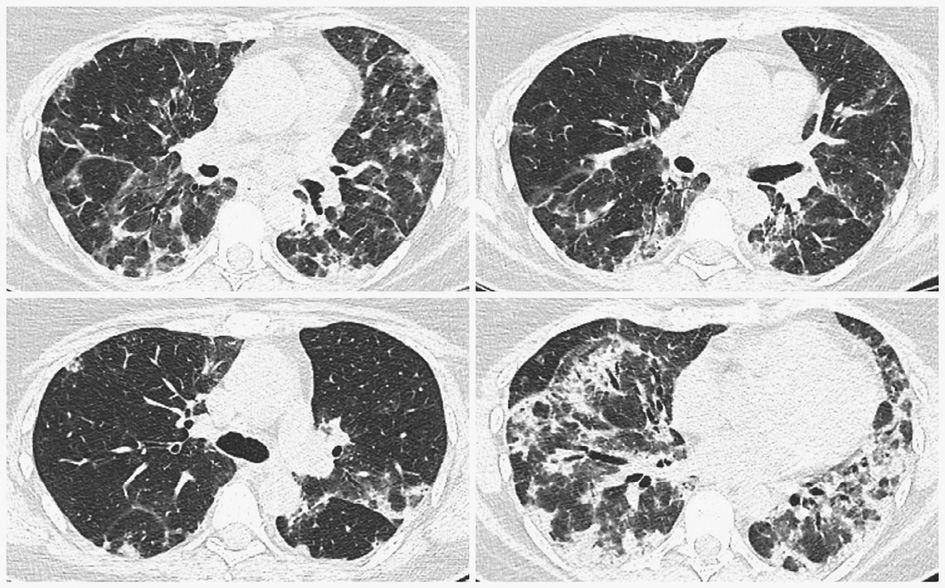

To specify possible causes of these symptoms, a thoracic CT was conducted and showed multiple bilateral confluent irregular foci mainly in the lower lobes, ground-glass appearance, and traction bronchiectasis, all suggesting interstitial lung disease (Figure 1).

Figure 1. Chest CT (2019.12.06) showing multiple bilateral confluent irregular opacities mainly in the lower lobes, ground-glass appearance, and traction bronchiectasis.